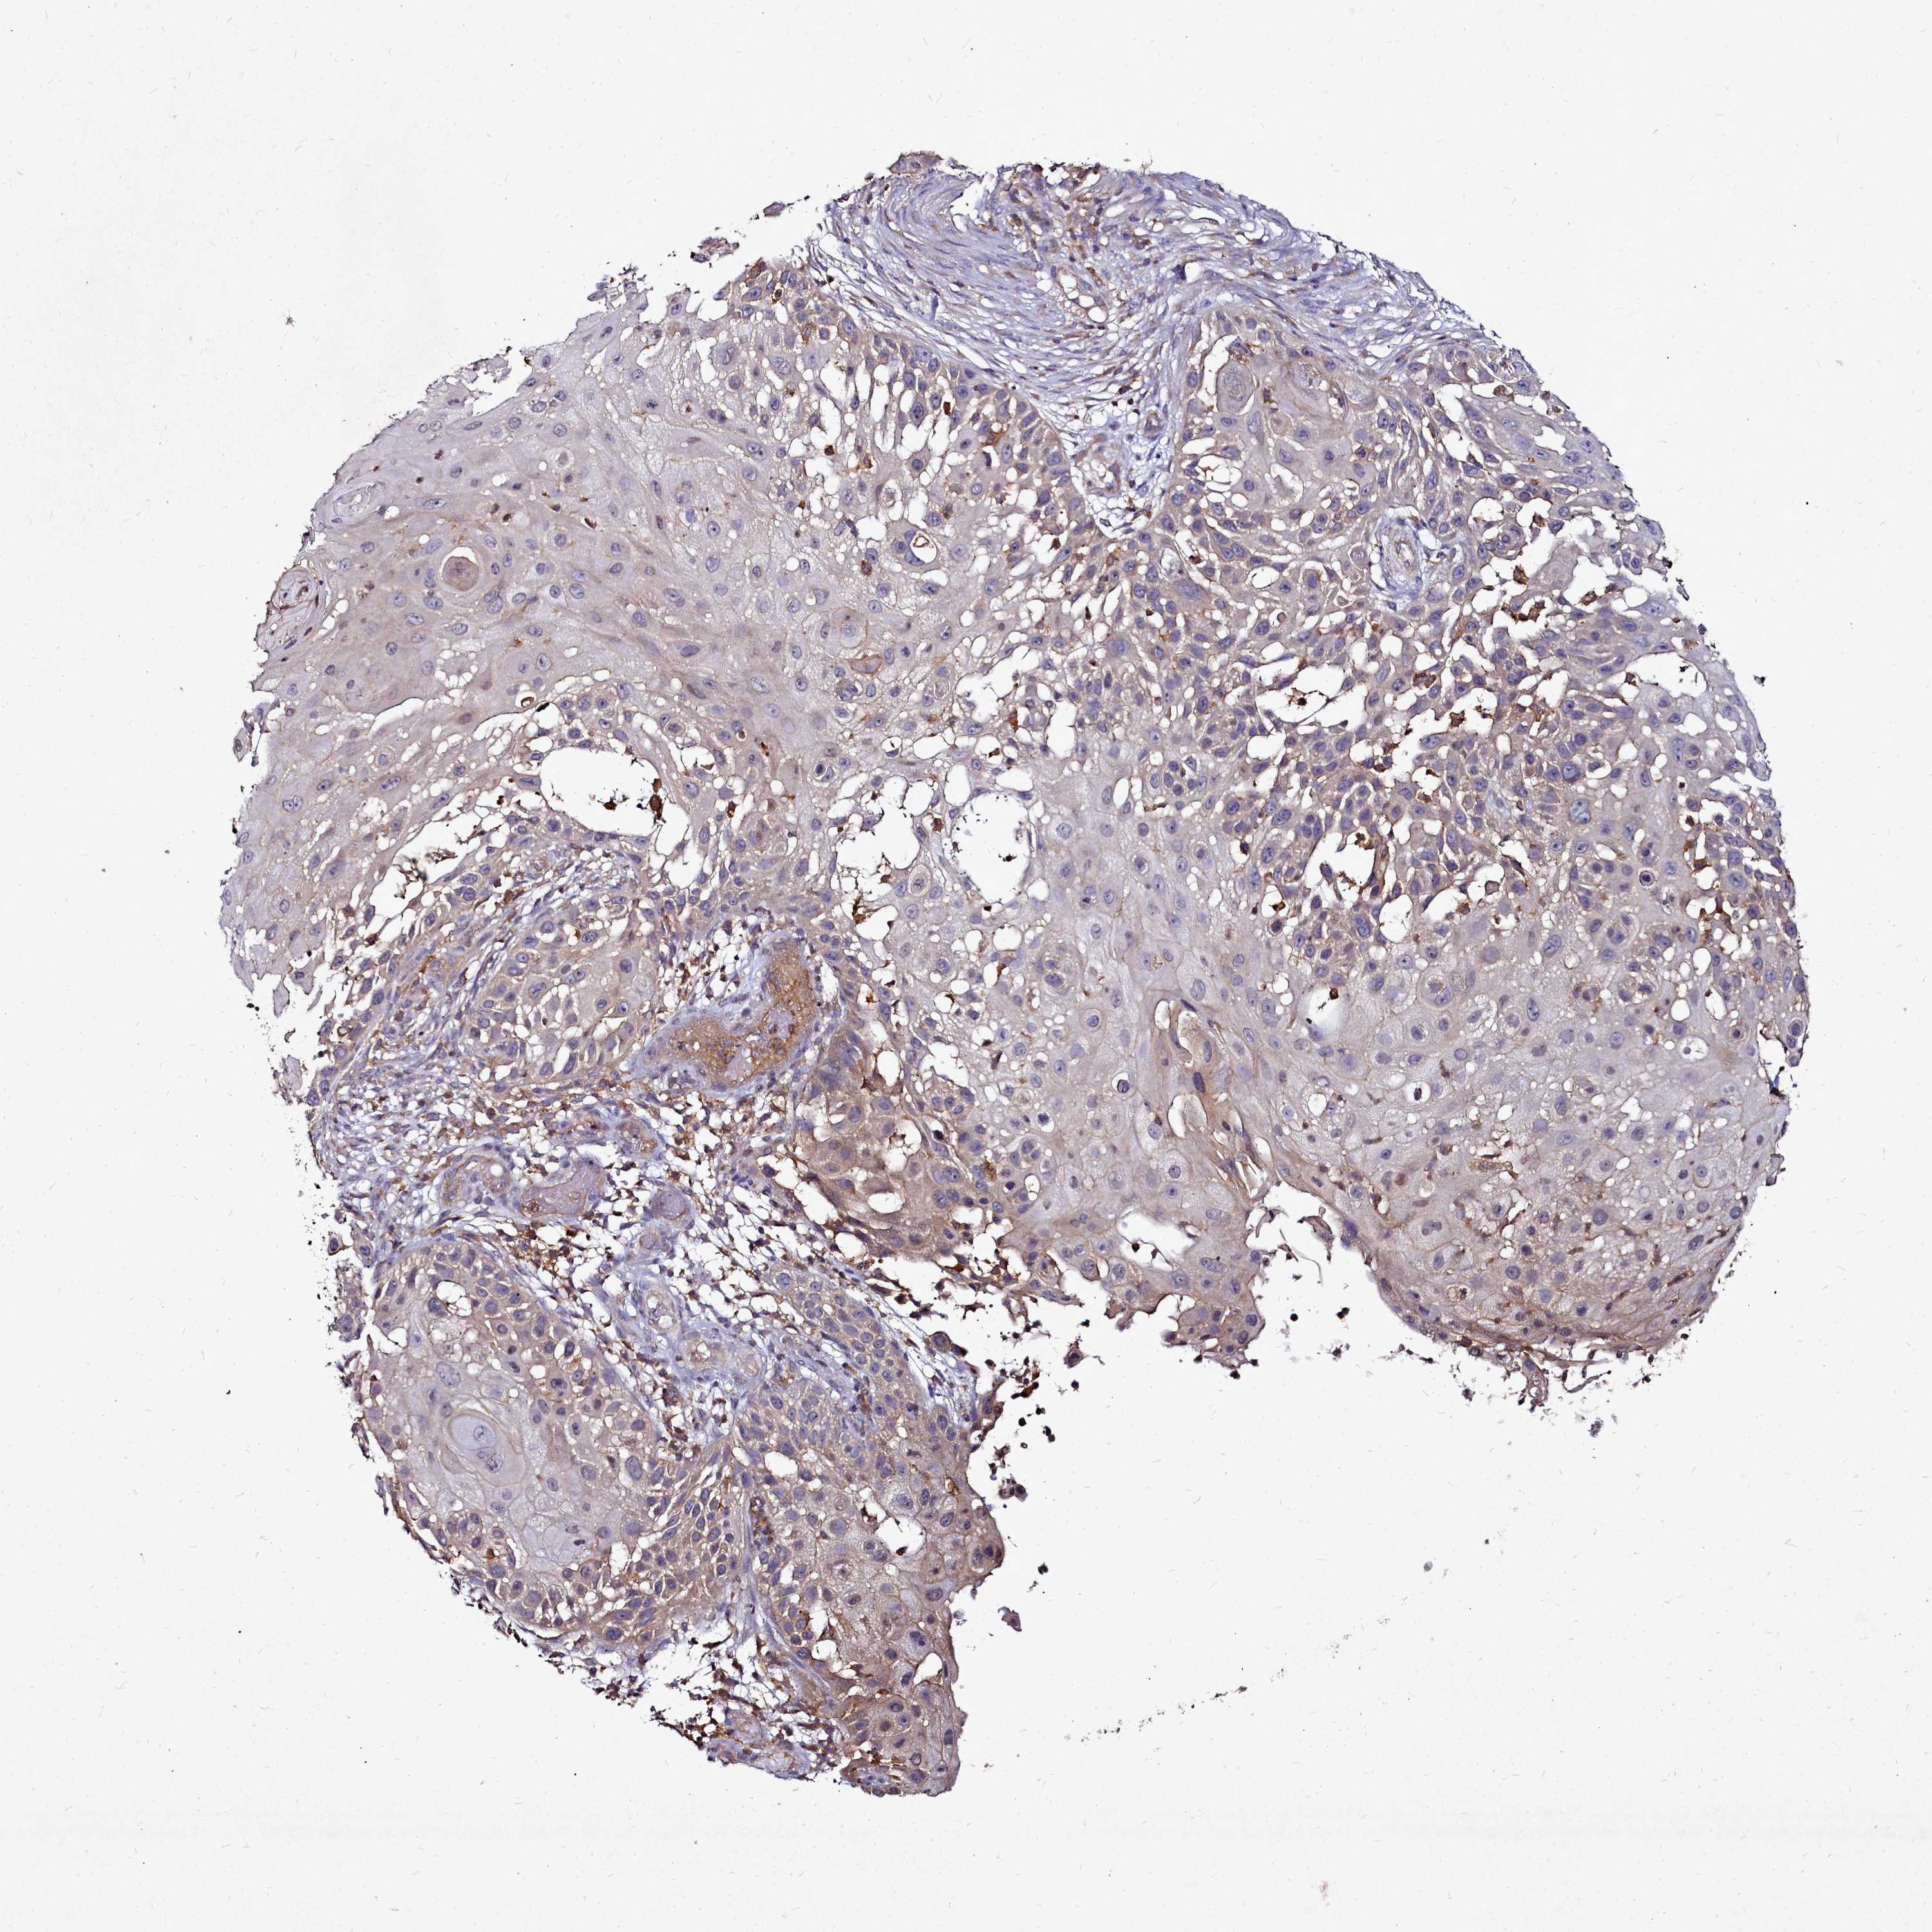

Basal cell and squamous cell cancer

SKIN CANCER - Protein expressioni

A mouse-over function shows sample information and annotation data. Click on an image to view it in a full screen mode. Samples can be filtered based on level of antibody staining by selecting one or several of the following categories: high, medium, low and not detected. The assay and annotation is described here.

Each image is clickable and will lead to virtual microscopy that enables deeper exploration of all samples and also displays staining intensity scores, fraction scores and subcellular localization as well as patient and tissue information for each sample.

Antibody HPA039490

Antibody HPA040772

Staining

High

Medium

Low

Not detected

Intensity

Strong

Moderate

Weak

Negative

Quantity

>75%

75%-25%

<25%

None

Location

Nuclear

Cytoplasmic/membranous

Cytoplasmic/membranous,nuclear

Basal cell carcinoma

Squamous cell carcinoma, NOS

Squamous cell carcinoma, metastatic, NOS